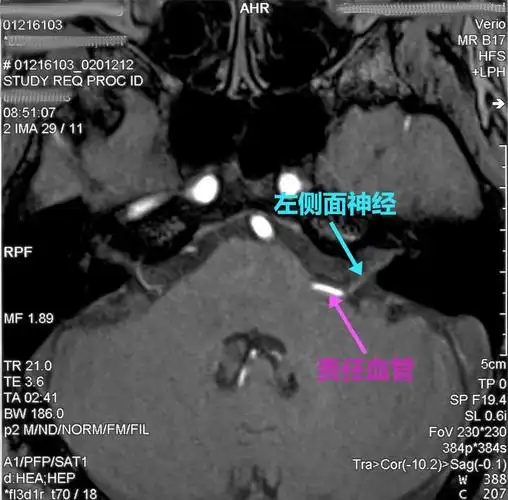

磁共振检查如3d-tof-mra,fiesta等,有助于明确责任血管和面神经之间的

面肌痉挛_检查_治疗方法_治疗方式 - 好大夫在线